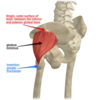

Hip muscles - superficial abductors and extensors

Gluteus maximus

Gluteus medius

Gluteus minimus

Tensor Fascia Lata

Gluteus maximus

origin - posterior surface of Ilium, sacrum, coccyx

insertion - Gluteal tuberosity of the femur, fascia lata

innervation - inferior gluteal nerve action

Gluteus medius

origin - iliac crest

insertion - lateral surface greater trochanter of femur

innervation - superior gluteal nerve

action - abductor, internal rotation

gluteus minimus

Origin- ilium

insertion - anterior greater trochanter of femur

innervation - superior gluteal nerve action - abductor hip, internal rotation

Tensor fascia lata

origin - anterior iliac crest, ASIS

insertion - iliotibial band ( which extends to popliteal fascia, lateral condyle of tibia)

innervation - femoral nerve

action - abductor and internal rotation

Role in tensing FASCIA LATA

Hip muscles - deep lateral rotators

Piriformis

Gemelli

Obturator internus

Quadratus femoris

Piriformis

origin - anterior surface of sacrum

insertion - greater trochanter of femur

innervation - nerve to piriformis

action - lateral rotation, abduction passes through the GREATER sciatic foramen